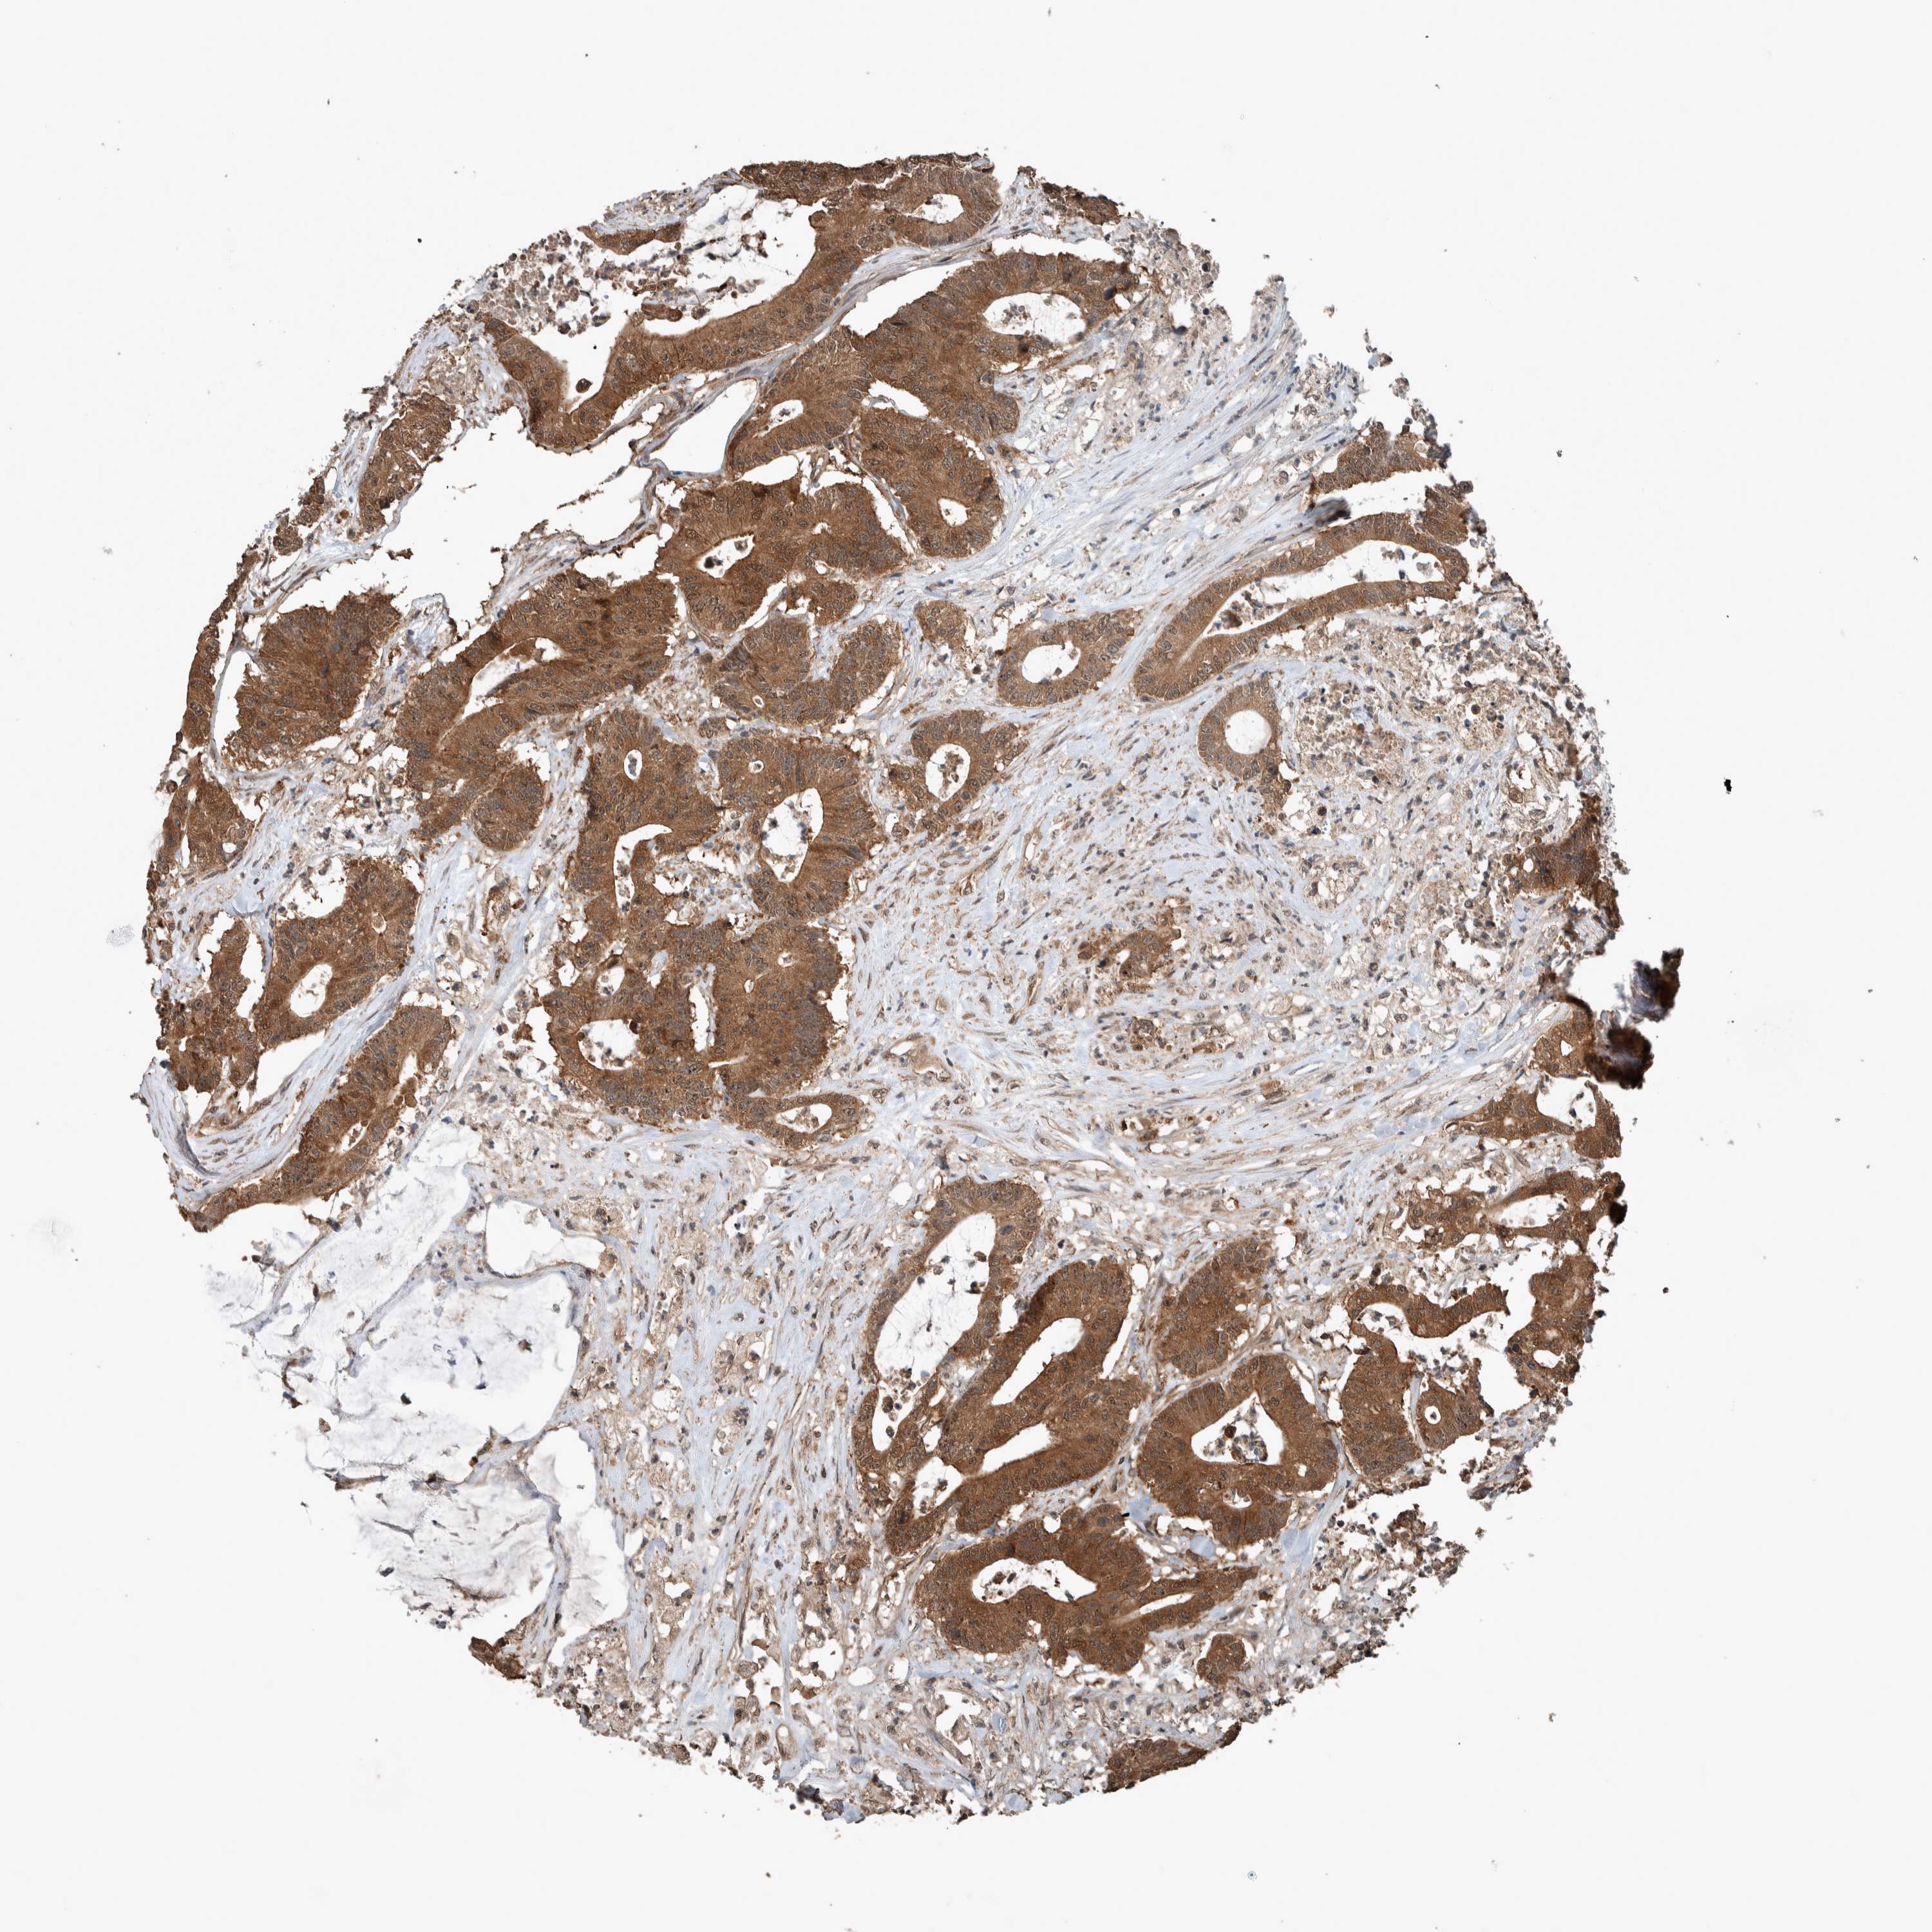

CANCER COLORECTAL CANCER Show tissue menu

Colorectal cancer

Human cancer

Colon adenocarcinoma